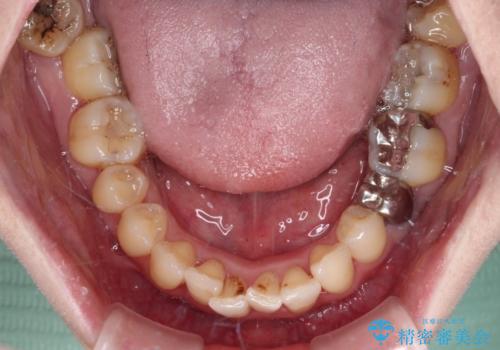

下顎前歯の叢生も気になっており、矯正治療も並行して進めていくこととしました。

検査を行ったところ、歯周外科処置や抜歯が必要と思われる箇所が散見されたため、あらためて当院に歯周病の初期治療から行うこととしました。